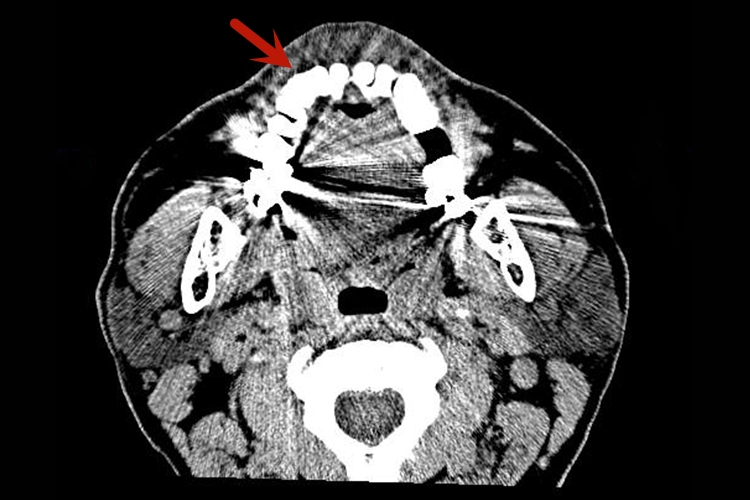

牙齿:牙齿分为牙冠、牙根、牙颈,牙髓腔为低密度,牙釉质骨质致密为高密度,牙本质及牙骨质密度稍低,牙槽骨牙周骨板密度高,骨松质呈网格状,牙周膜为牙根与牙槽骨硬骨板之间的连续线状低密度影。

下颌骨:下颌骨分为一体两支,下颌支与体连接成钝角,即下颌角。下颌骨体部上缘为齿槽骨,体部有下颌管,宽约3mm,升支中部舌侧面有下颌孔,升支上方有下颌切迹及两个突起,前方为喙突,后方为髁状突。

颞颌关节:颞颌关节间隙位于关节凹和髁状突之间,呈低密度影,关节间隙宽度在2mm以上,上间隙最宽,后间隙次之,前间隙最窄,两侧相等。髁状突呈椭圆形密度高的影像,由连续、整齐、致密白线围绕。开口位时,髁状突位于关节结节下方或前下方,闭口位髁状突位于关节凹内。